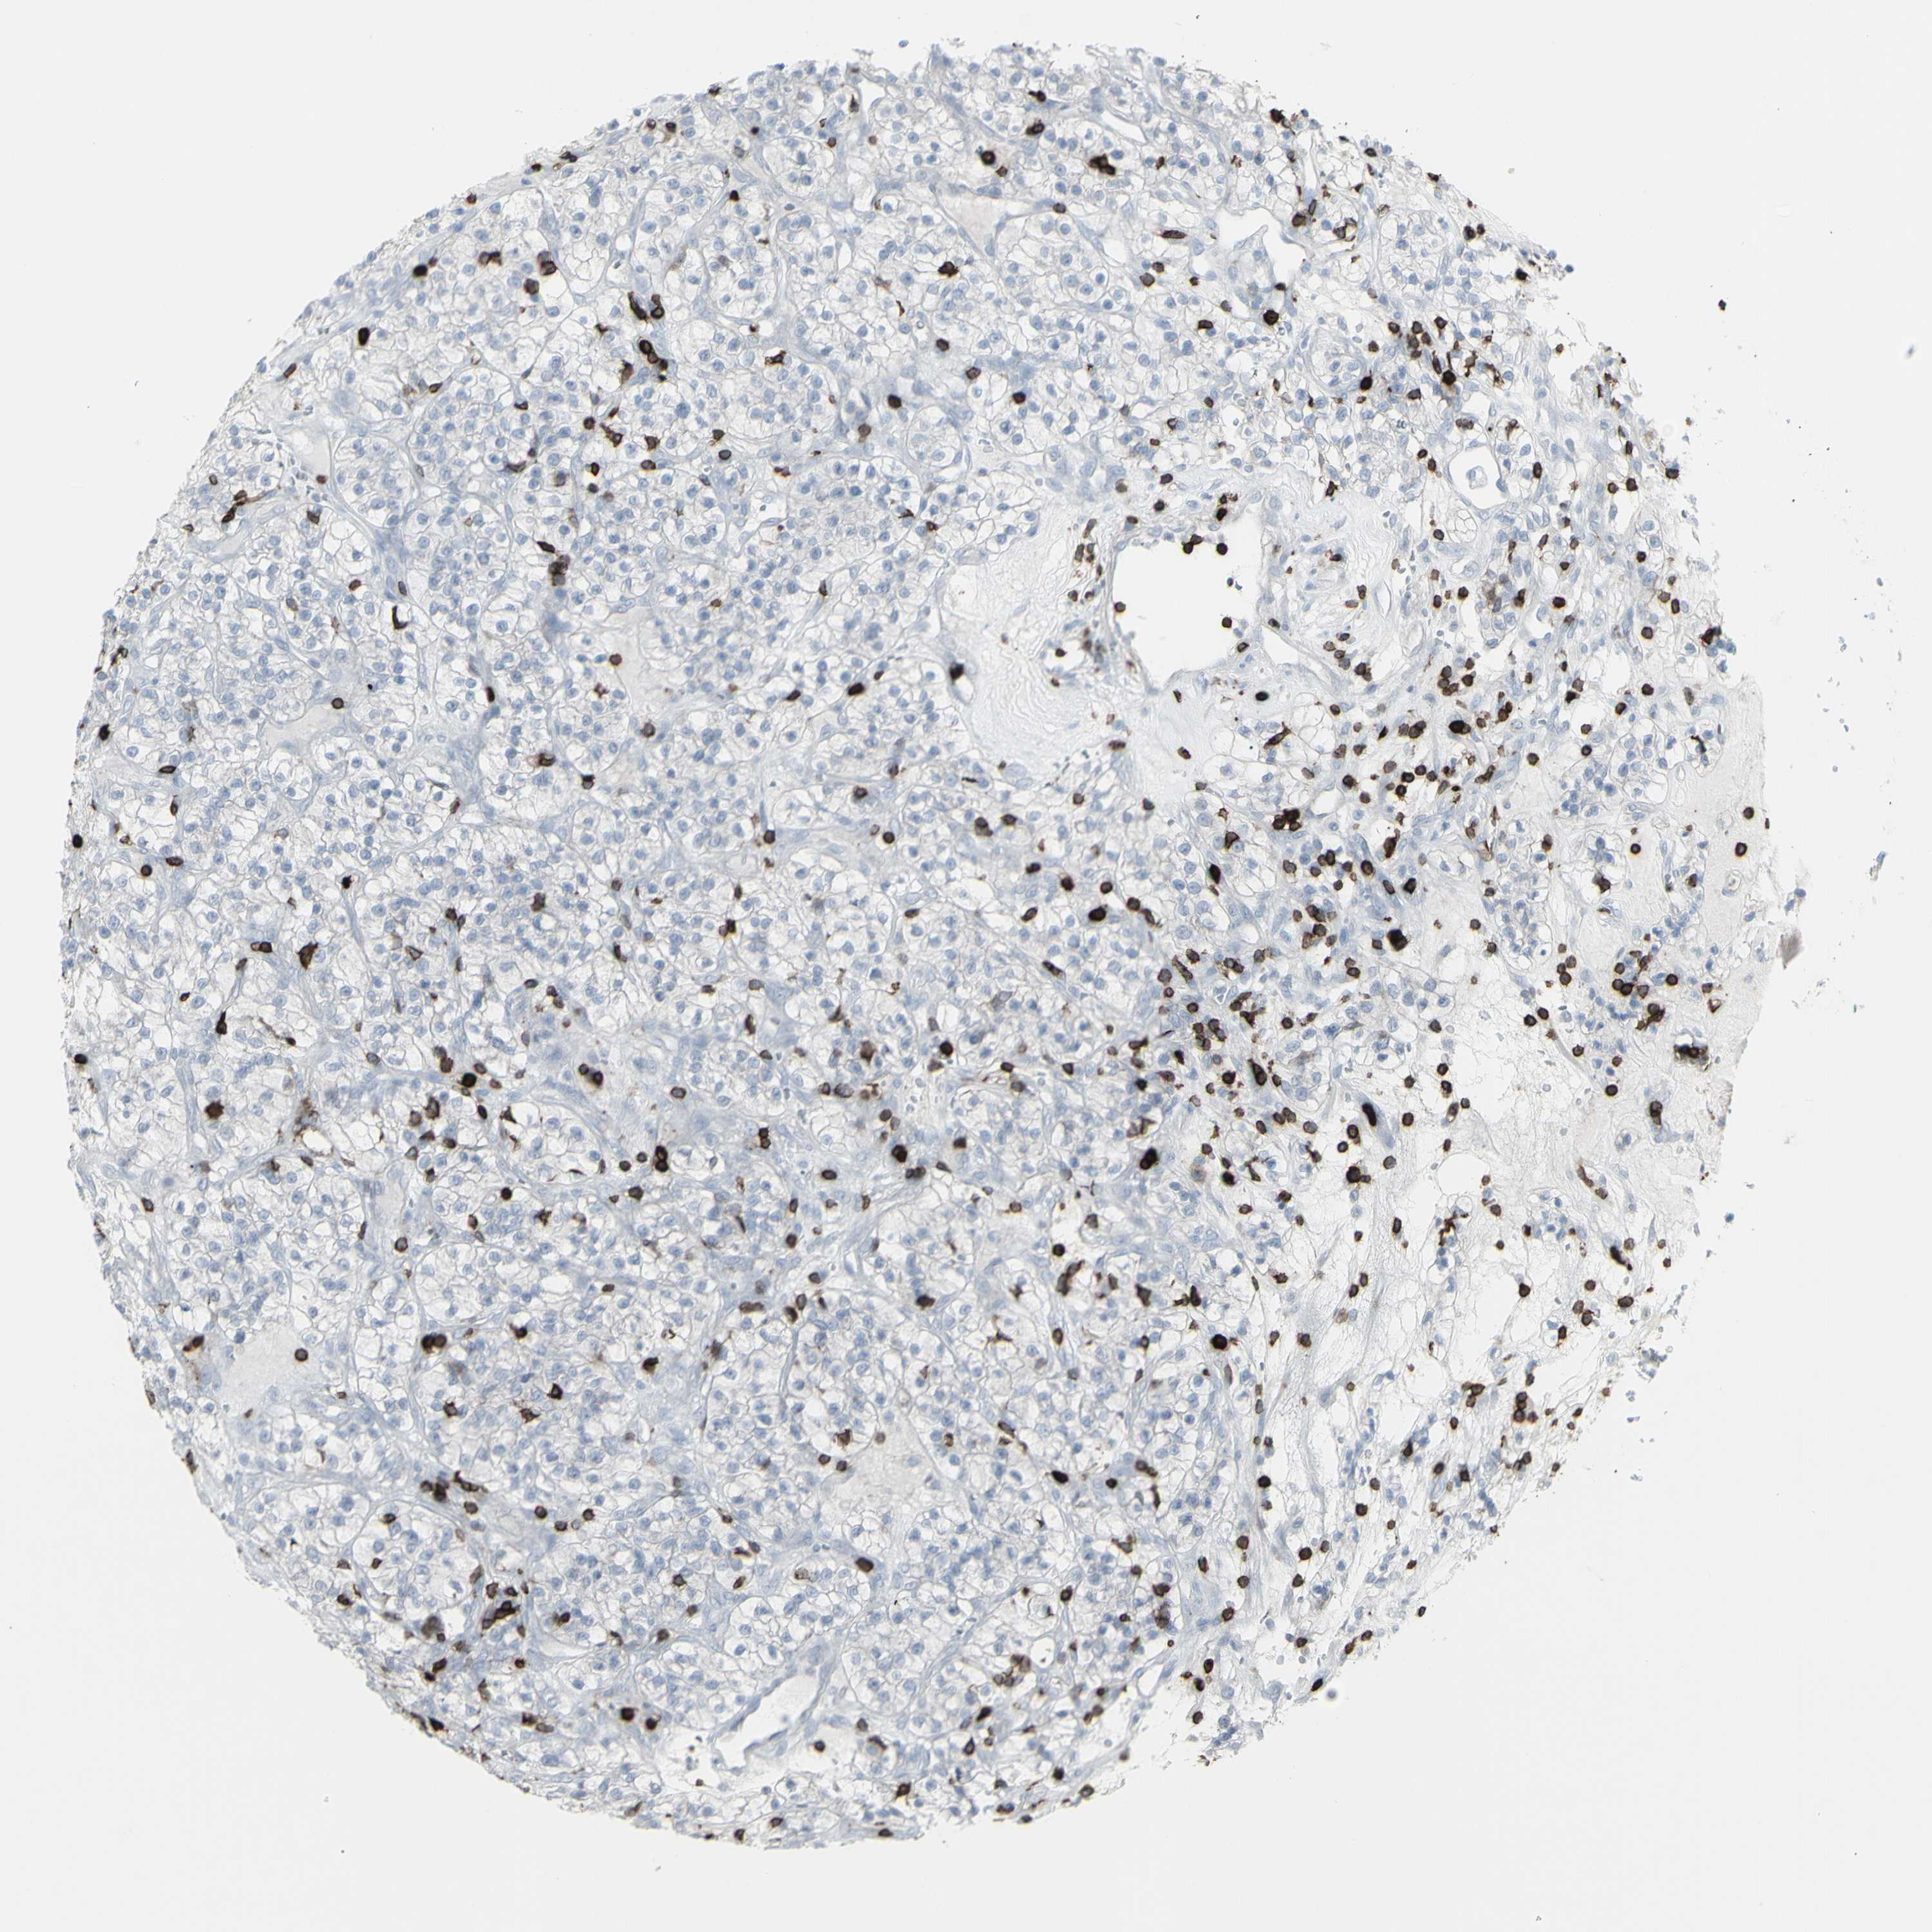

KIDNEY RENAL CLEAR CELL CARCINOMA (VALIDATION) - Interactive survival scatter ploti

The Survival Scatter plot shows the clinical status (i.e. dead or alive) for all individuals in the patient cohort, based on the same data that underlies the corresponding Kaplan-Meier plots. Patients that are alive at last time for follow-up are shown in blue and patients who have died during the study are shown in red.

The x-axis shows the expression levels (FPKM) of the investigated gene in the tumor tissue at the time of diagnosis. The y-axis shows the follow-up time after diagnosis (years). Both axes are complimented with kernel density curves demonstrating the data density over the axes. The top density plot shows the expression levels (FPKM) distribution among dead (red) and alive patients (blue). The right density plot shows the data density of the survived years of dead patients with high and low expression levels respectively, stratified using the cutoff indicated by the vertical dashed line through the Survival Scatter plot. This cutoff is automatically defined based on the FPKM cutoff that minimizes the p-score. The cutoff can be changed by dragging the vertical line or by entering a cutoff value in the square labeled "Current cut-off".

Under the Survival Scatter plot the p-score landscape (black curve; left axis) is shown together with dead median separation (red curve; right axis). Dead median separation is the difference in median mRNA expression between patients who have died with high and low expression, respectively. It is calculated as follows: median FPKM expression of dead patients with high expression - median FPKM expression of dead patients with low expression. This is intended to aid the user in visually exploring custom cutoffs and the associated p-scores and dead median separation.

Individual patient data is displayed and can be filtered by clicking on one or more of the category buttons on the top of the page. Categories describing expression level and patient information include: high, low, alive, dead, female, male and tumor stages. The scale of the x-axis can be toggled between linear and log-scale by clicking on the "x log" button. Mouse-over function shows TCGA ID, patient information and mRNA expression (FPKM) for each patient.

& Survival analysisi

Kaplan-Meier plots summarize results from analysis of correlation between mRNA expression level and patient survival. Patients were divided based on level of expression into one of the two groups "low" (under cut off) or "high" (over cut off). X-axis shows time for survival (years) and y-axis shows the probability of survival, where 1.0 corresponds to 100 percent.

CD247 is not prognostic in Kidney Renal Clear Cell Carcinoma (validation)

Best expression cut offi

Based on the FPKM value of each gene, patients were classified into two groups and association between prognosis (survival) and gene expression (FPKM) was examined. The best expression cut-off refers the FPKM value that yields maximal difference with regard to survival between the two groups at the lowest log-rank P-value. Best expression cut-off was selected based on survival analysis .

When clicking on this number, the vertical dashed line indicating cut-off, the interactive survival plot, and the Kaplan-Meier curve will be adjusted to show results based on the best expression cut-off.

: 14.81

P scorei

Log-rank P value for Kaplan-Meier plot showing results from analysis of correlation between mRNA expression level and patient survival.

N/A

TCGA RNA samplesi

RNA-seq data is reported as average FPKM (number Fragments Per Kilobase of exon per Million reads), generated by the The Cancer Genome Atlas (TCGA) .

Normal distribution across the dataset is visualized with box plots, shown as median and 25th and 75th percentiles. Points are displayed as outliers if they are above or below 1.5 times the interquartile range. FPKM values of the individual samples are presented next to the box plot.

Average pTPM 11.7

Number of samples 100